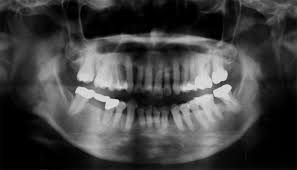

あなたの歯は何本ありますか?虫歯治療を何本していますか?神経をとった歯がありますか?歯を抜いた事のある人は、虫歯や歯周病になりやすい人です。また、虫歯になりやすく治療が、手後れになると神経をとる治療になります。神経をとるようになった人は、歯の寿命が短くなるのでより注意が必要です。パノラマレントゲンは、あなたの歯の履歴をみることができます。そこから、今後の注意点が見えてきます。歯はあなたの資産です。歳をとった時に資産がないのは、悲しく苦しいことです。定期的なレントゲンの検査と歯ブラシの方法やタイミング、食生活など生活習慣の見直しであなたの資産を守りましょう。